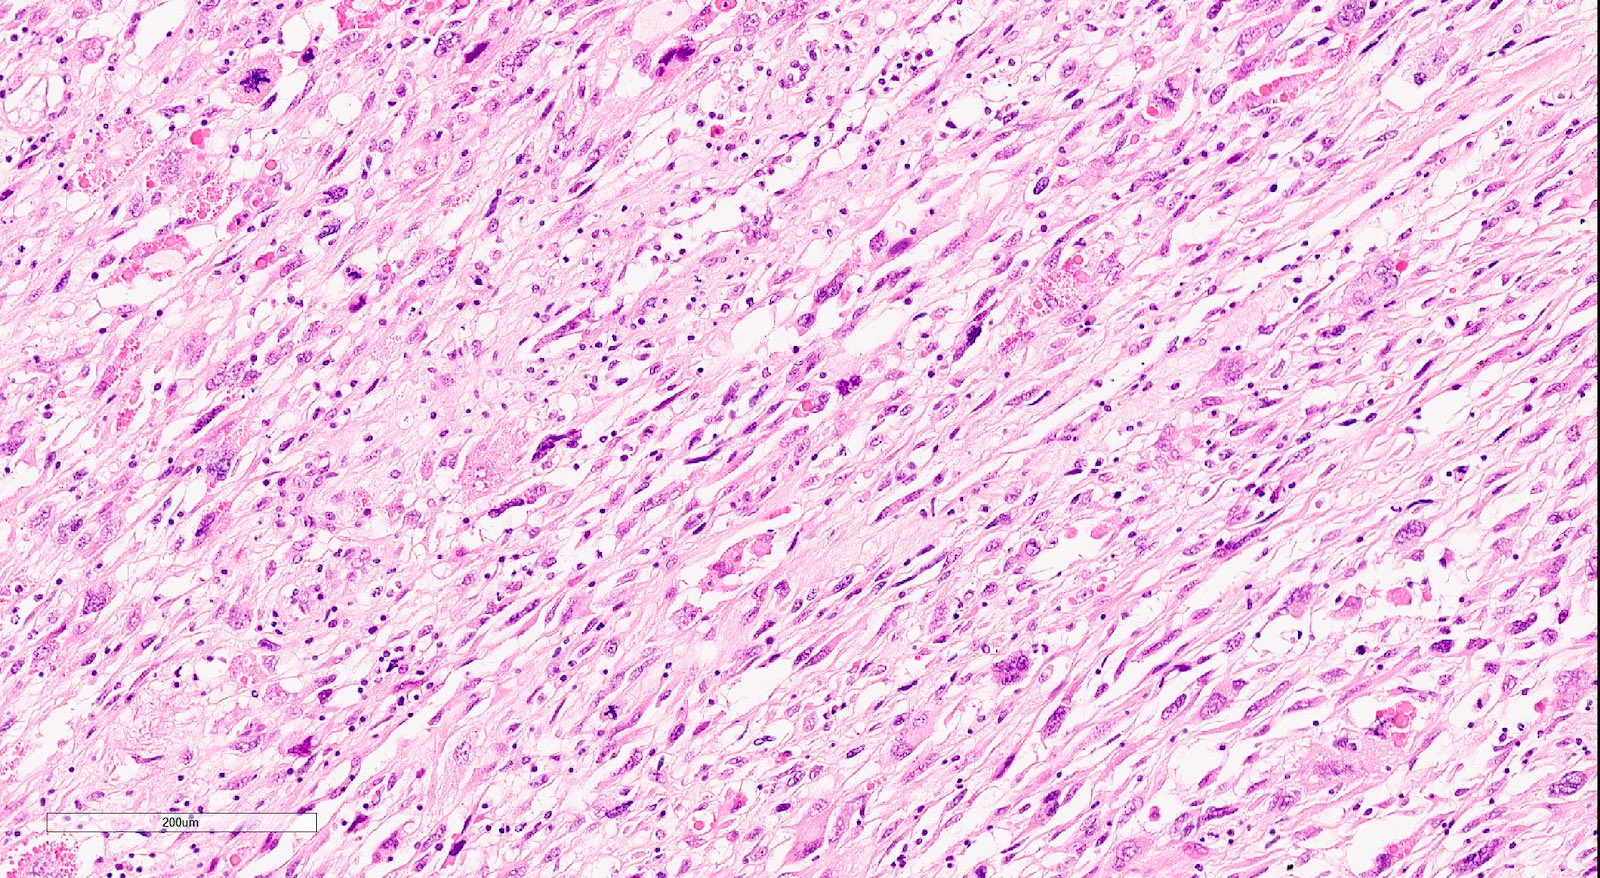

- Sarcomatous elements:

- Often spindle and pleomorphic

- 50% contain heterologous elements (most commonly rhabdomyosarcoma and chondrosarcoma) (Am J Surg Pathol 2007;31:1653)

- Osteosarcomatous, liposarcomatous and angiosarcomatous differentiation are less common (Semin Diagn Pathol 1988;5:199, Arch Pathol Lab Med 1991;115:583, Int J Gynecol Pathol 2017;36:140)

Microscopic (histologic) images